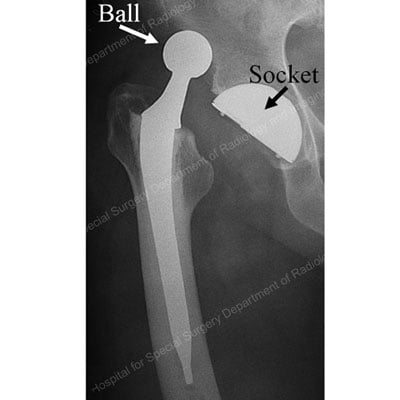

X-ray of a total hip replacement showing the ball, socket and stem implants.

X-ray of a primary total hip replacement showing the ball, socket and stem implants